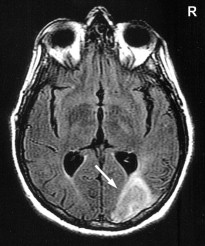

Stroke Syndrome:

“Dejerine and Roussy” Syndrome - Thalamic (on this case on the right). Infarction of sensory relay nucli due to occlusion of thalamogeniculates. These come from the PCA